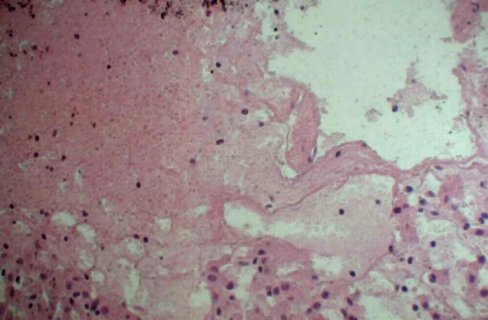

¸ÎÔà×ϰ߲¡